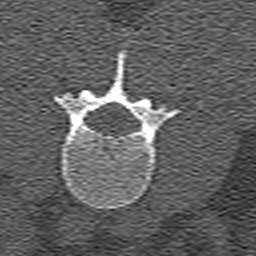

2D segmentation. Our model is compared with two methods based on domain adaptation: AdaptSegNet [16] and SIFA [2]. AdaptSegNet and SIFA are trained with the officially released codes. AdaptSegNet is trained with Dice loss as we only have one class here. The results are summarized in Fig. 6 and Table 2(a). AdaptSegNet invokes DeeplabV2 as the segmentor and cannot capture the vertebra especially when metal artifacts exist. SIFA outputs plausible predictions but the performance is heavily affected by the metal artifacts. Also, the segmentations predicted by SIFA can not capture vertebrae precisely and show false positive bones and enlarged masks (see red arrows in Fig. 6). With joint learning, our model achieves the best segmentation performance with an average Dice of 0.847 and an average ASD of 1.54mm.

Modality translation and artifact reduction. Here we compare our model with other methods: CycleGAN [21], DRIT [8], ADN [9]. All the models are trained with our data using their officially released codes. Further, we train a UNet segmentation network using annotated CT data and apply it to synthesized CT images as an anatomy-invariant segmentation evaluator. As shown in Table 2(b), our model achieves the best performance with a much larger average Dice compared with other methods. Fig. 6 shows the synthetic images and segmentation results. CycleGAN and DRIT tend to output plausible and realistic CT images but are not able to preserve the anatomical information precisely. As shown by the red arrows in Fig. 6, the bony structures appear distorted and noisy. ADN can retain most of the anatomical information but not for the bone pixels with high intensity, which might be classified into metal artifacts. With anatomical knowledge learned from the CT domain, our model outputs high-quality synthetic CT images while keeping anatomical consistency.

For artifact reduction, ADN and DRIT [8] could not successfully recover the clean images and streak artifacts remain in the synthetic image (see blue arrows in Fig. 6). CycleGAN [21] could output clean images but the distorted bones make them less valuable. Our model can suppress all the artifacts and keep the bone edges sharp, which outperforms all the other methods.